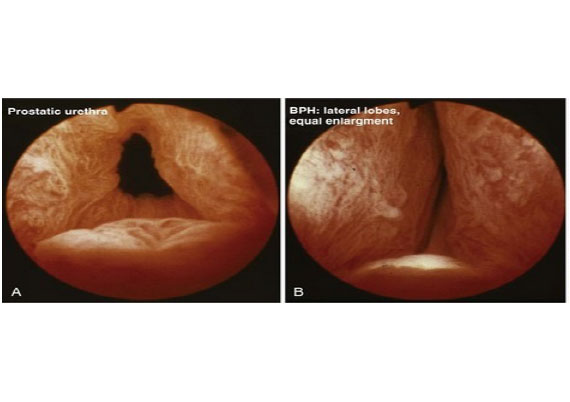

BPH explanation and diagram

The prostate is a gland that sits at the exit of the bladder. In a young man it is 15-25 cc in volume. Imagine it as a ring donut, with urine passing through the donut hole in the centre. As one grows older, the donut often enlarges, and the hole at the centre closes off, obstructing the flow of urine. This happens most commonly due to a benign process where abnormal tissue growth expands from the centre part of the prostate, replacing the normal central tissue, and compressing the normal glandular tissue at the edge of the prostate gland. This is termed BPH- Benign Prostate Hyperplasia.